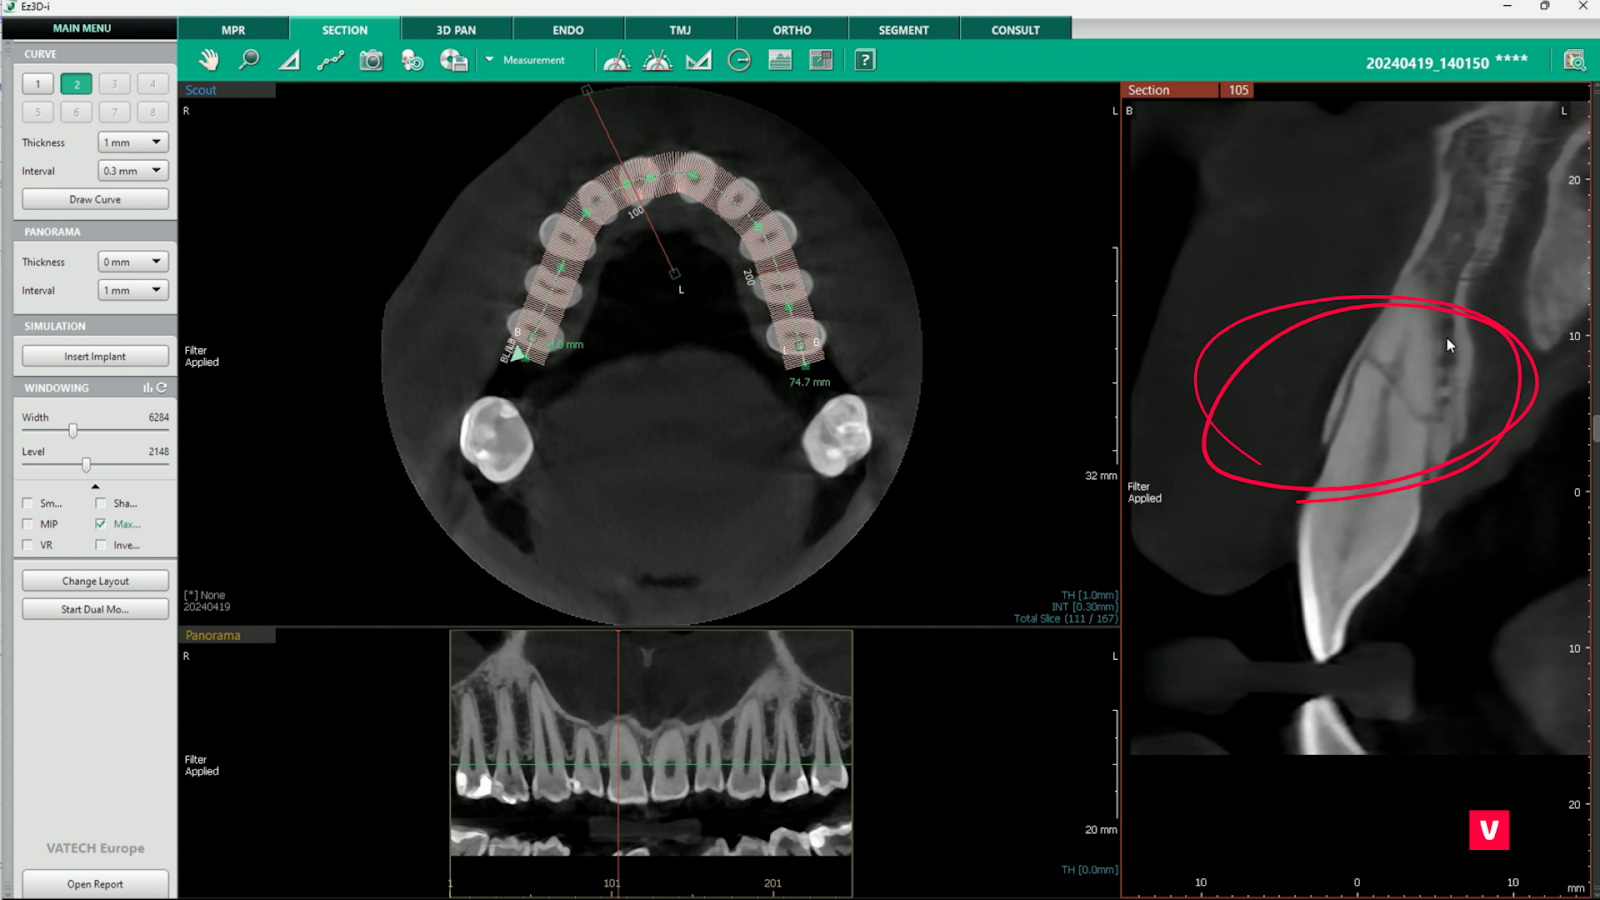

2. Filtrul Max Sharpen

Filtrul Max Sharpen este una dintre ajustările oferite de tabul SECTION pentru cea mai bună afișare posibilă a imaginilor. Acest filtru permite o claritate superioară a contururilor imaginii.

De asemenea, în tabul SECTION există un glisor care reglează luminozitatea imaginii și unul pentru reglarea contrastului. Astfel, imaginile sunt redate pe mai multe niveluri de claritate, la fel și posibilitatea de inversare alb-negru.

Panoul de control al tabului SECTION este foarte intuitiv și ajută în stabilirea unui diagnostic corect.

cbct dinte fractura

3. Modificarea aspectului

Tabul SECTION are, de asemenea, o mulțime de posibilități atunci când vine vorba de aspectul imaginii pe care îl puteți utiliza în timpul procesului de diagnosticare. Sunt disponibile opțiuni de personalizare pentru o identificare detaliată a patologiilor dentare.

În cazul studiului de caz prezentat, problema pacientului a fost destul de evidentă odată ce s-a făcut secționarea în plan coronal, astfel încât modificările aspectului nu au fost atât de necesare pe cât ar putea fi în cazuri mai complicate.